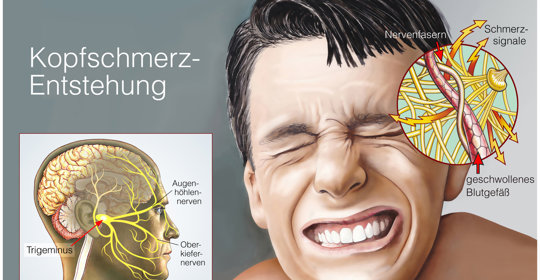

劇烈頭痛:頭部的急救信號,症狀及科學調理方法詳解

搏動性頭痛:腦海的地雷,症狀揭秘與緩解方法

後腦勺陣痛:瞭解症狀、原因、治療與舒緩小技巧